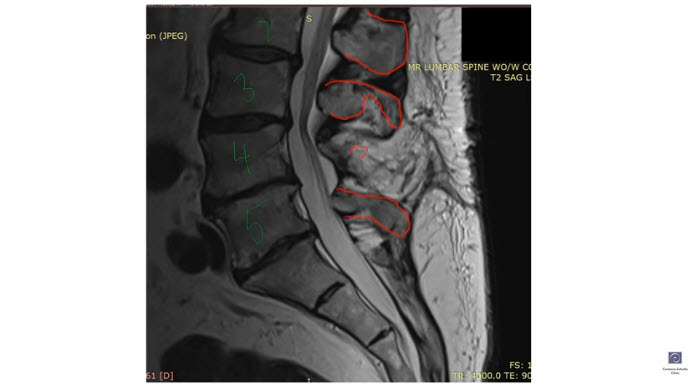

With this wide laminectomy, the surgeon removed the L4 spinous process and part of the lamina (vertebral bone) to open up the spinal canal. With the L4 spinous process gone, the spinous ligaments were no longer attached from L3 down to L5. Also, the multifidus muscle was no longer attached, causing it to essentially “die”.

That’s exactly what happened to this patient. His leg pain returned, and the post-surgery MRI showed why the pain returned. The surgery had essentially destabilized the supportive structures in that part of his lumbar spine, leading to more back and leg pain.